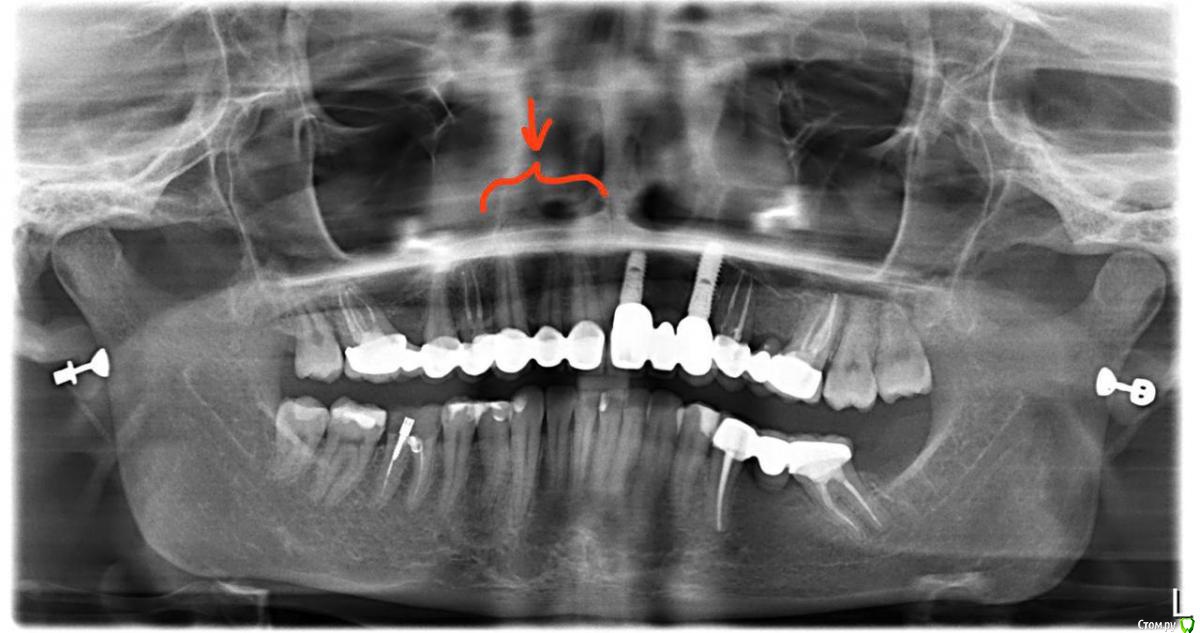

chervoncevdaniil Опубликовано 21 декабря, 2019 Поделиться Опубликовано 21 декабря, 2019 У вас точно только 3 соединены,Правая сторона точно не вместе с передними?потвашему описанию похоже на расцементировку одной из опорных коронок Ссылка на комментарий

krokomot Опубликовано 22 декабря, 2019 Поделиться Опубликовано 22 декабря, 2019 Наличие запаха из под коронок при удовлетворительной гигиены наводит на мысль об их расцементировке, желательно сделать прицельные снимки этих зубов. Расцементировка показание к снятию конструкции. Но вы должны понимать, что по снимкам и фотографиям мы не можем точно определить, что это расцементировка. Обратитесь к доктору изготовившему конмтукцию со своими жалобами. Ссылка на комментарий

Polika-polika Опубликовано 24 декабря, 2019 Автор Поделиться Опубликовано 24 декабря, 2019 (изменено) У вас точно только 3 соединены,Правая сторона точно не вместе с передними?потвашему описанию похоже на расцементировку одной из опорных коронокА почему похоже на расцементеровку? из-за щелчков или из-за запаха? Врач в Москве смотрел, ковырялся и сказал, что хорошо прилегает, правда без прицельного снимка это было.. Точно только 3 соединены в этом местеСпасибо всем за ответы Изменено 24 декабря, 2019 пользователем Polika-polika Ссылка на комментарий